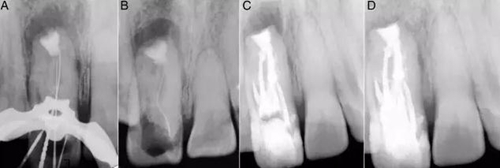

在討論完治療風險和成本等相關事項后患者簽署了知情同意書。橡皮障隔離,局部麻醉下開放髓腔,去除齲壞和腐爛的牙體組織。在清洗完冠部通道后用牙髓探針DG16來定位根管口。逐漸去除牙膠的同時用3%次氯酸鈉沖洗(圖1C)。隨后在釉牙骨質(zhì)界附近發(fā)現(xiàn)了兩個主要根管開口,并用手用擴孔挫2、3和4擴大。用10#和15#k銼探索直到遇到阻礙。用17%EDTA和3%次氯酸鈉沖洗。在初步?jīng)_洗和暫封后,病人拍攝了CBCT,顯現(xiàn)了牙體內(nèi)部形態(tài)的3維結(jié)構(gòu)(2A–K)。復診在牙科顯微鏡下探查根管,發(fā)現(xiàn)近中根管口通向一個寬的Oehlers III型b的牙內(nèi)陷(MI)。遠中根管口通向2個根管,近遠中根管(DM)根管和遠中根管,還有一個在最遠中部分的盲袋。盲袋是Oehlers II型的第二類牙內(nèi)陷(DI),因為它終止在根中1/3。此外,還發(fā)現(xiàn)了近中切角處一個近中根管(M) (圖3A and B)。一共發(fā)現(xiàn)了5個根管并且他們之間互有交通。所有的根管除了DI都終止于一個大口徑的根尖孔。因此,牙齒被診斷為雙重牙內(nèi)陷,包含Oehlers III型b和II型。牙髓根尖周病變被診斷為慢性根尖膿腫。

圖2:A:腭部近中到遠中可以看到兩個根管(MI和D)和一個盲袋;B:唇部可以看到另外兩個根管(M和DM);C和D:矢狀面可以看到環(huán)形的牙內(nèi)陷;E:寬髓室和窄M根管;F:4個根管,分別命名為M、MI、DM、D;G:盲袋DI;H:根尖有兩個根管口;I:大口徑根尖孔;J:3維上頜牙弓唇部形態(tài);K:牙內(nèi)陷腭部形態(tài)。